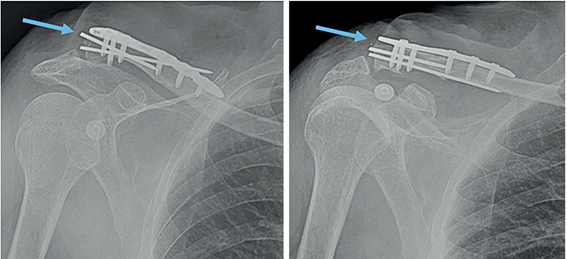

Paciente masculino de 76 años, dominancia derecha, quien ingresó a urgencias por caída desde su propia altura. Al examen físico presentaba deformidad en la clavícula derecha y las radiografías mostraron fractura desplazada del tercio distal de la clavícula (Figura 1), por lo que fue llevado a cirugía para reducción abierta, fijación interna con placa anatómica bloqueada de clavícula y fijación con dos clavos de Kirschner. La radiografía postquirúrgica mostró material de osteosíntesis con adecuada reducción de la fractura (Figura 2). El paciente evolucionó satisfactoriamente, se dió de alta con analgésicos orales y citó a control por consulta externa.